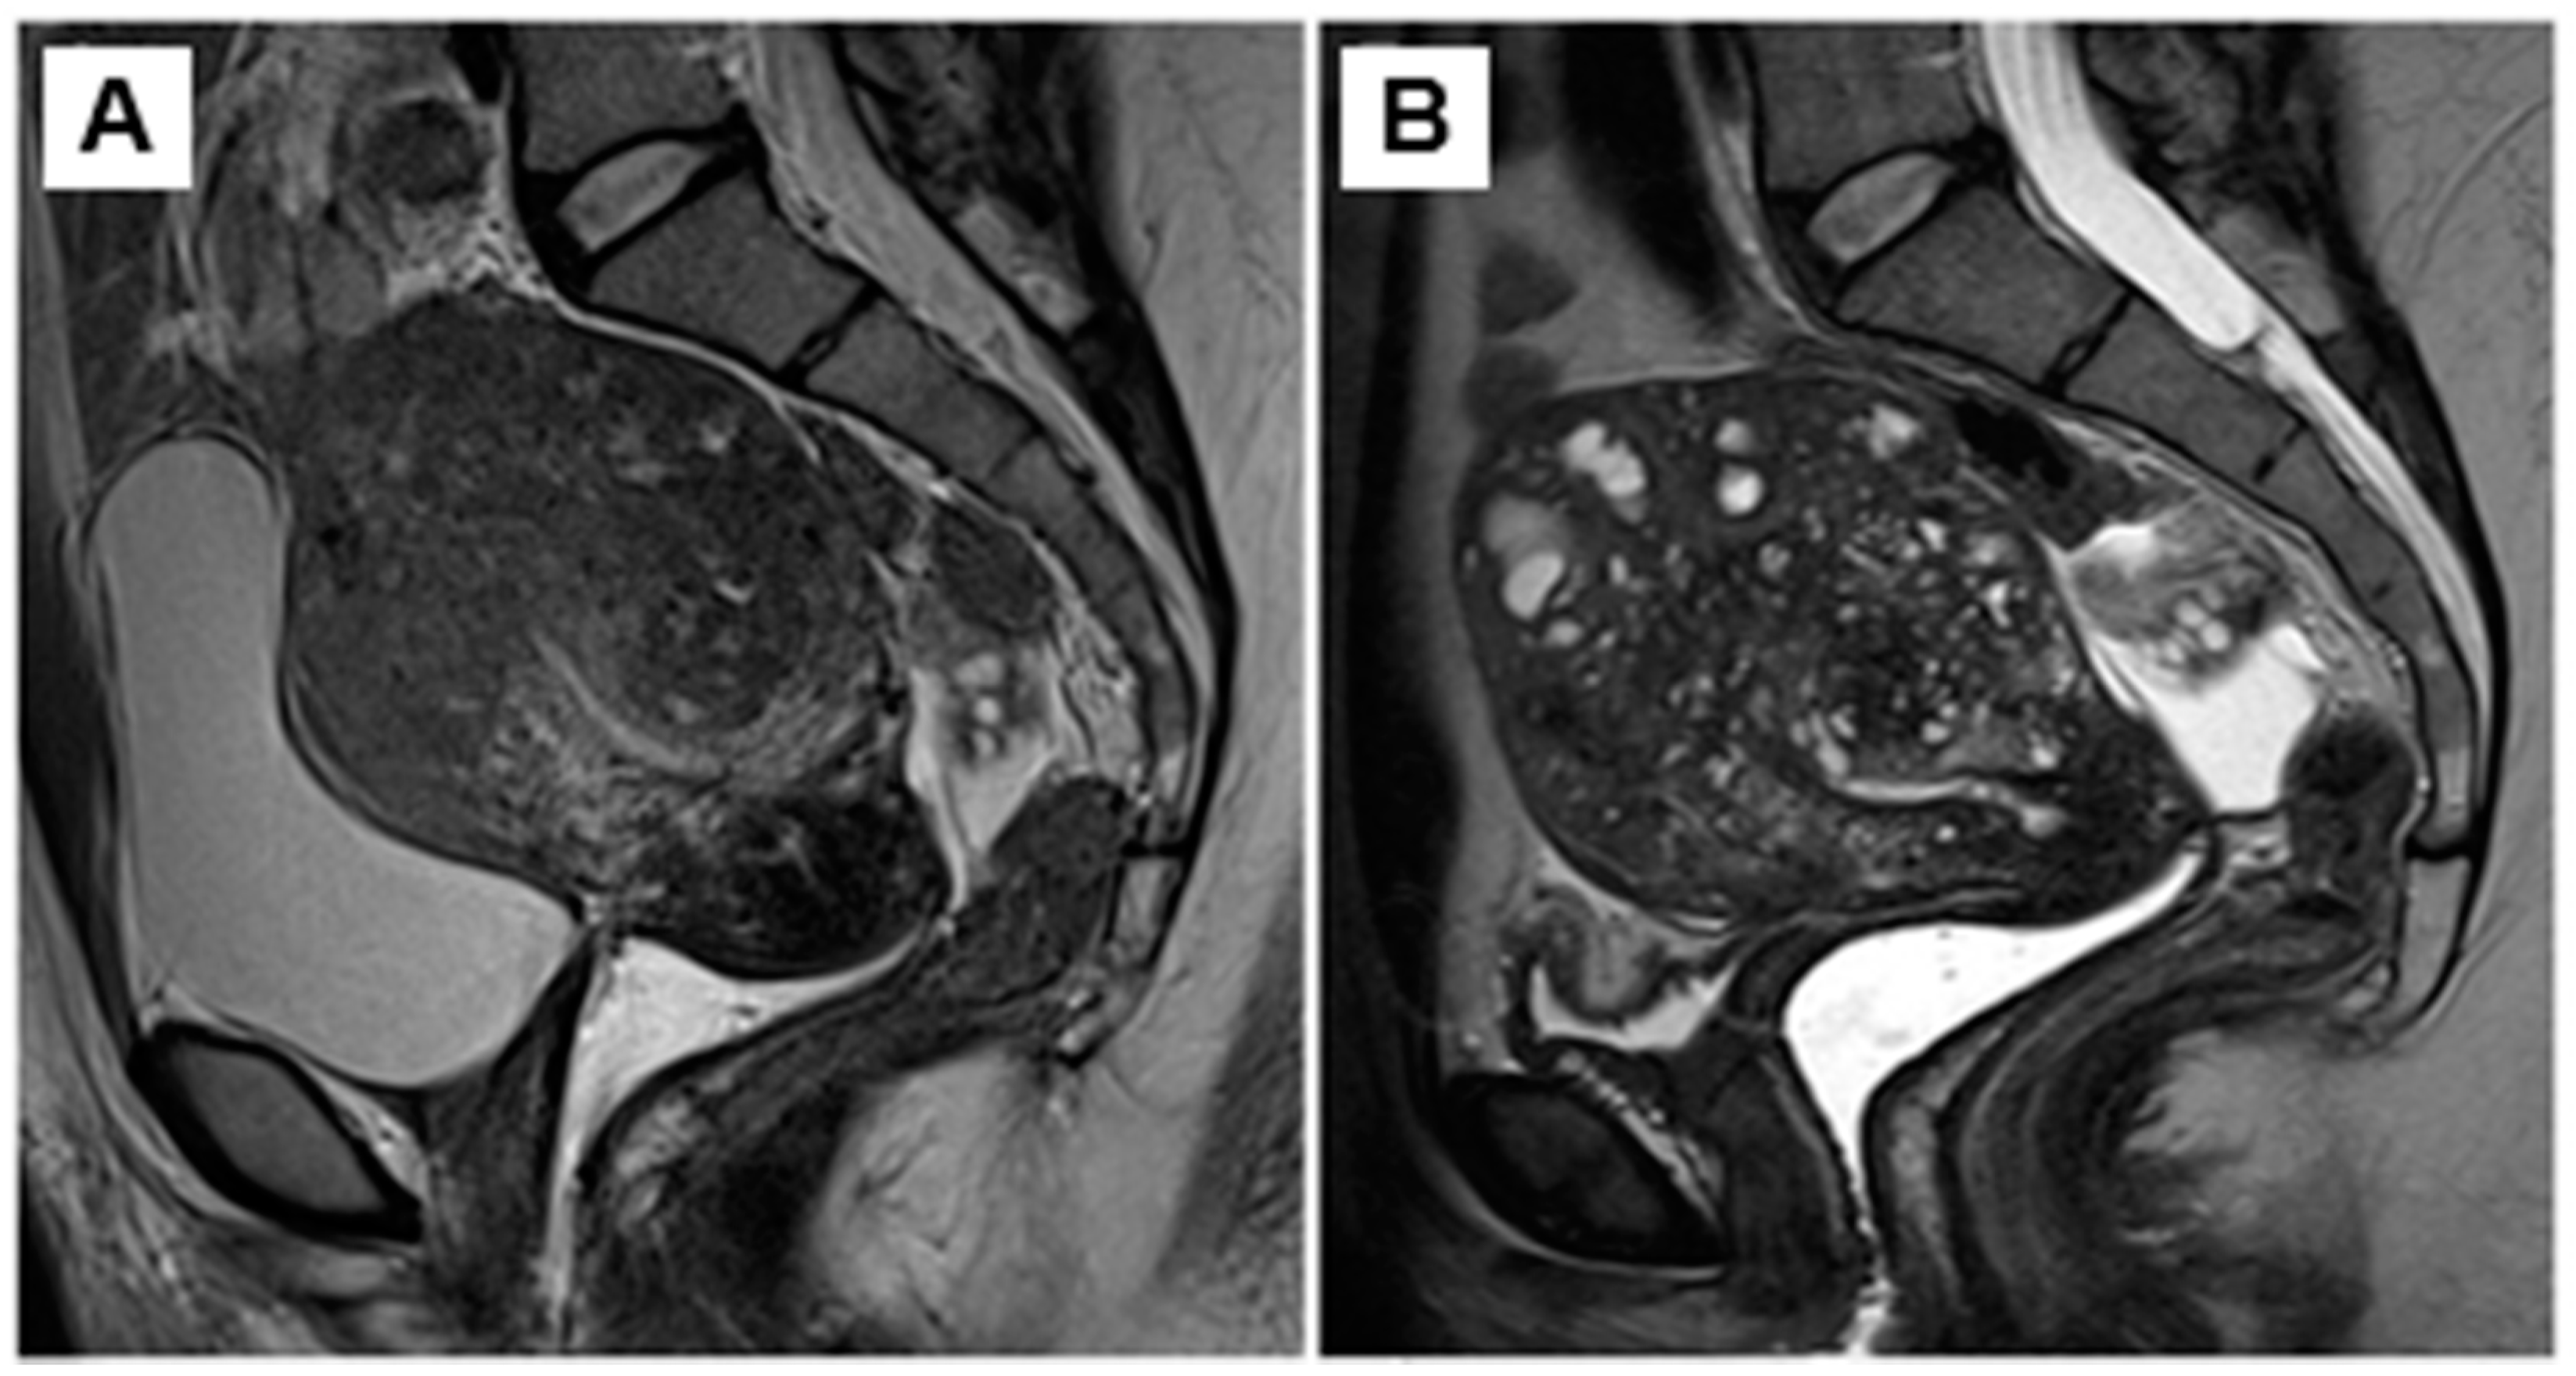

- Imaoka, I.; Ascher, S.M.; Sugimura, K.; Takahashi, K.; Li, H.; Cuomo, F.; Simon, J.; Arnold, L.L. MR imaging of diffuse adenomyosis changes after GnRH analog therapy. J. Magn. Reason. Imaging 2002, 15, 285–290. [Google Scholar] [CrossRef]

- Andersson, J.K.; Pozzi Mucelli, R.; Epstein, E.; Stewart, E.A.; Gemzell-Danielsson, K. Vaginal bromocriptine for treatment of adenomyosis. Impact on magnetic resonance imaging and transvaginal ultrasound. Eur. J. Obstet. Gynecol. Reprod. Biol. 2020, 254, 38–43. [Google Scholar] [CrossRef] [PubMed]